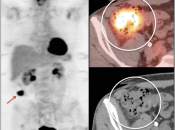

Metastases:

The most common sites of metastatic disease include the lymph nodes (regional & distant), liver, lung, peritoneal cavity, bones, brain and adrenal glands.

Recurrence & Restaging: (Most common indication)

- Rising tumor markers & negative (or indeterminate) CT scan.

- Restaging known recurrence, especially if surgery is contemplated.

- Distinguishing recurrence from post-therapeutic inflammation/scarring.